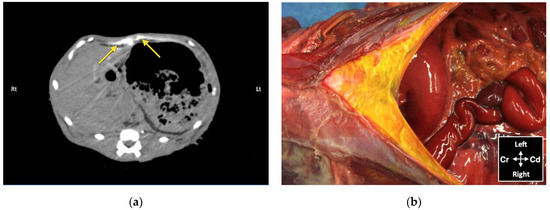

Figure 7. Computed tomography (CT) image showing the distribution of 0.5 mL/kg bupivacaine–iopamidol–dye solution administered by two approaches of the TAP injection in a cat; a TAP-L injection was performed in the left (Lt) hemiabdomen and a TAP-SL in the right (Rt) hemiabdomen; WL 50, WW 350. Ventral is at the top of the image.

Contrast solution was identified in the target fascial plane in eight TAP-L and eight TAP-SL (Figure 7). Following all 16 lateral TAP injections, the contrast solution distribution was assessed as “possible partial intramuscular infiltration in the m. transversus abdominis” and following 7 out of 16 lateral TAP injections (3 TAP-L and 4 TAP-SL) as “possible focal spread between the mm. obliquus internus and externus abdominis”. Focal (1.5 mm) intraperitoneal contrast solution was observed following two lateral TAP injections (1 TAP-L and 1 TAP-SL). In 2 TAP-SL, contrast solution was observed within the falciform ligament fat (Figure 8a). Contrast solution was not observed in the abdominal cavity or organs.

Figure 8. Bupivacaine–iopamidol–dye distribution in the falciform ligament following subcostal TAP injection (TAP-SL approach) in a cat cadaver: (a) Transverse CT image showing injectate distribution ventral to the m. transversus abdominis and dorsal to the liver and the stomach (yellow arrows); WL 50, WW 350. Right (Rt) is to the left (Lt) of the image and ventral is at the top of the image; (b) Anatomical dissection of the same cat showing injectate distribution in the ligament after incision of skin, subcutaneous tissue and linea alba; Cd, caudal; Cr, cranial.